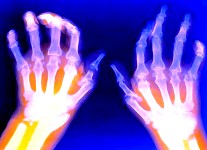

Los científicos ya han regenerado con éxito las articulaciones de las extremidades de animales con células madre, dando así una esperanza a los pacientes con artritis y articulaciones que necesitan reemplazarse.

En un nuevo estudio publicado en la revista The Lancet, los investigadores de Columbia University Medical Center, la Universidad de Missouri y la Universidad de Clemson, se dice que fueron regeneradas las articulaciones de conejos con células madre del propio conejo.

Esta sería la primera vez que articulaciones de las extremidades se han regenerado a partir de las células madre del propio animal. Siendo este un avance importantísimo ya que jamás había sido hecho antes.

En los conejos este reemplazo de las articulaciones tardó solo 3 semanas, siendo que hasta ahora las personas con las articulaciones dañadas deben obtener un reemplazo metálico que dura sólo de 10 a 15 años.